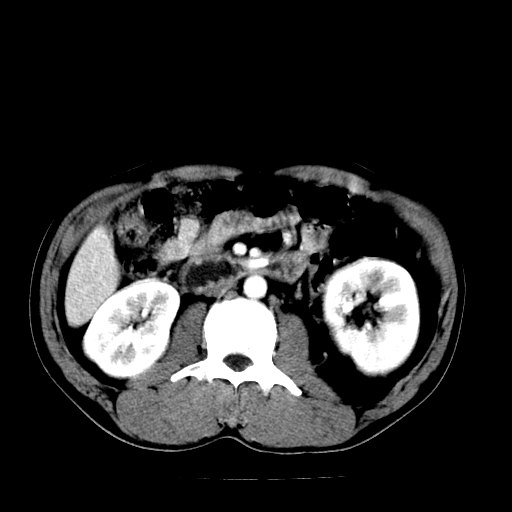

以下是引用天南地北在2007-4-30 13:36:00的发言:[br]支持慢性胰腺炎伴有假性囊肿

以下是引用andymaomao在2007-4-30 14:28:00的发言:[br]支持:1.慢性胰腺炎并假性囊肿形成可能;[br] 2.左肾形态稍增大,旋转不良。